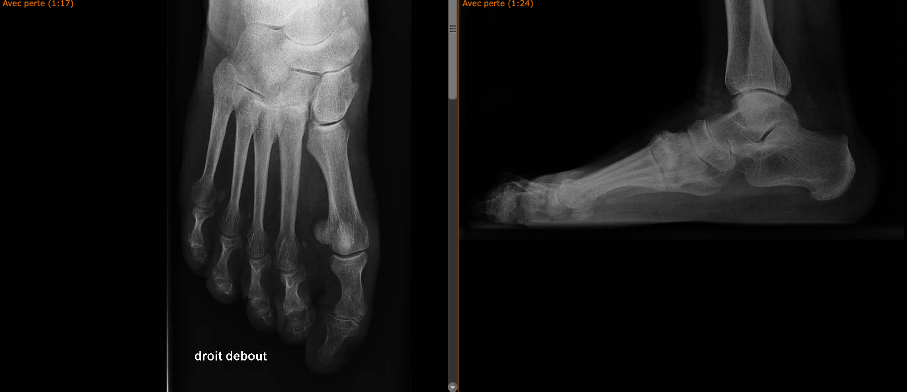

The clinical articles in this issue address four distinct domains. Knee revision surgery is examined through the application of 3D printed models, exploring their role in preoperative planning and intraoperative guidance. The diagnosis and therapeutic management of posterior shoulder dislocation are subsequently reviewed, followed by a focused analysis of trauma to the Lisfranc joint. The issue concludes with a critical appraisal of artificial intelligence in knee arthroplasty, considering its implications for surgical decision-making and outcome optimization.